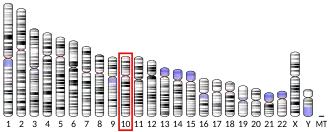

Urokinase is encoded in humans by the PLAU gene, which stands for "plasminogen activator, urokinase".[7] The same symbol represents the gene in other animal species.

- ^ a b c GRCh38: Ensembl release 89: ENSG00000122861 – Ensembl, May 2017

- ^ a b c GRCm38: Ensembl release 89: ENSMUSG00000021822 – Ensembl, May 2017